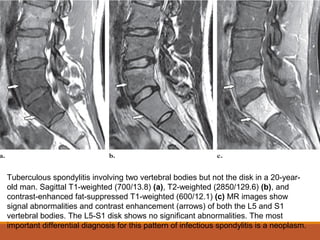

Tuberculous spondylitis involving two vertebral bodies but not the disk in a 20-year-

old man. Sagittal T1-weighted (700/13.8) (a), T2-weighted (2850/129.6) (b), and

contrast-enhanced fat-suppressed T1-weighted (600/12.1) (c) MR images show

signal abnormalities and contrast enhancement (arrows) of both the L5 and S1

vertebral bodies. The L5-S1 disk shows no significant abnormalities. The most

important differential diagnosis for this pattern of infectious spondylitis is a neoplasm.